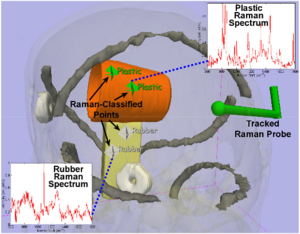

- 4.39 Using Stress MRI to Analyze the 3D Changes in Apical Ligament Geometry from Rest to Maximal Valsalva: A Pilot Study